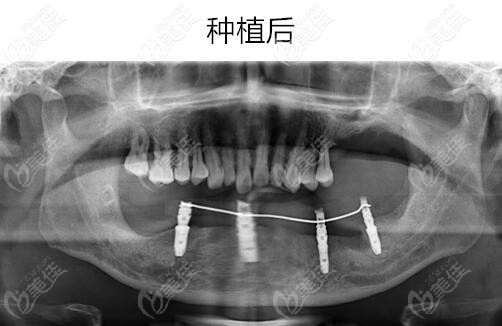

【宁波牙博士王道军院长微创即刻种植牙真人案例效果图片】

技术简介:微创即刻种植牙技术,是国外牙博士齿科集团20多年临床与科研的精华,以安全性、微创性、精准性、即刻性和高成功率在齿科种植修复界独树一帜。该技术依托口腔数字化工作平台,在具有丰富临床经验的医生操作下,通过全新3D全景CT扫描定位立体成像,计算出患者缺牙部位的牙骨组织情况,准确计算出种植牙的位置、角度、深度,做到量体裁衣一气呵成。